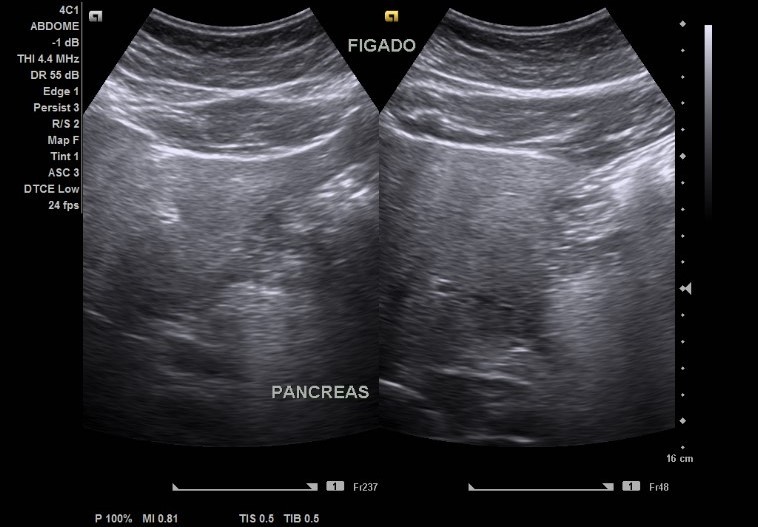

Exames de Ultrassonografia

Exames de Ultrassonografia

Exames de Ultrassonografia

Exames de Ultrassonografia

Exames de Ultrassonografia

Exames de Ultrassonografia